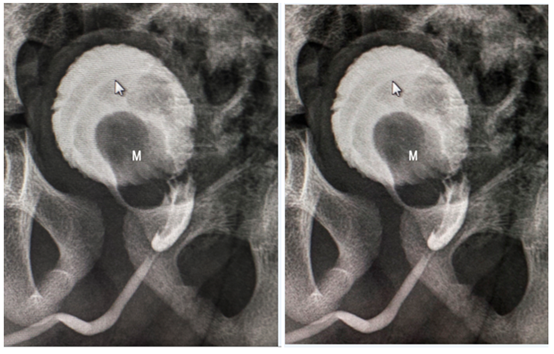

A three-year-old child, a third-pregnancy product with no relevant history, is admitted to the urology service of the pediatric hospital of Centro Habana due to haematuria and intermittent difficulty in urination, which lasted 3 months. The physical and complementary blood tests were not relevant, so the pediatrician referred him to the radiology department to perform abdominal ultrasound which reported the presence in the pelvic excavation a solid well-defined echogenic mass measuring 7.1 x 6.0 x 5.5 cm in intimate relationship with the prostate and indistinguishable from said structure, which elevates the bladder floor, with areas that cannot be defined if they are intravesical. Color Doppler shows vascularization in both the interior and the periphery of the lesion, associated with slight bilateral ureterohydronephrosis predominantly left, without demonstrating other positive findings by such examination. Figure 1 Subsequently, retrograde and voiding urethrocystography was performed, which showed a mass with growth inside the bladder in frontal and oblique projection, which impresses independently of its wall, which causes a defect in the floor of the bladder with a polylobulated appearance. Measures described. Figure 2 and 3 A presumptive diagnosis of bladder tumor is established, with differential diagnoses as early childhood extravesical tumors such as rhabdomyosarcoma and benign tumors of the lower urinary tract (leiomyoma, fibroma, neurofibroma, hemangioma), the latter extremely rare, as well as bladder polyps. A cystoscopy was performed to establish a diagnosis (for suspicion of bladder injury), to evaluate characteristics of the lesion and to obtain a sample for biopsy.

Figure 2 Mictric urethrocystography in left anterior oblique projection showing a full defect (M) that seems to originate from the anterior region of the prostatic urethra, without obstructing its light, which grows lobularly inside the bladder (solid white arrow).

Figure 3 Cystography in frontal projection showing a polylobulated fullness defect in the bladder floor (*) as well as slight left vesicoureteral reflux (arrow).